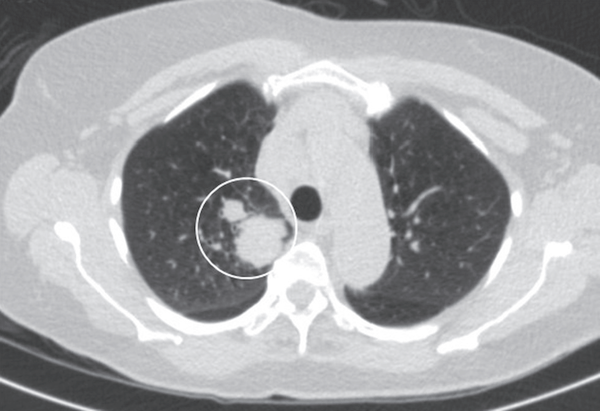

(胸部ct示:右上叶一个4.

胸部平片和 ct 图片来源:ncbi

患者胸部ct示双肺病变(2019年4月29日)